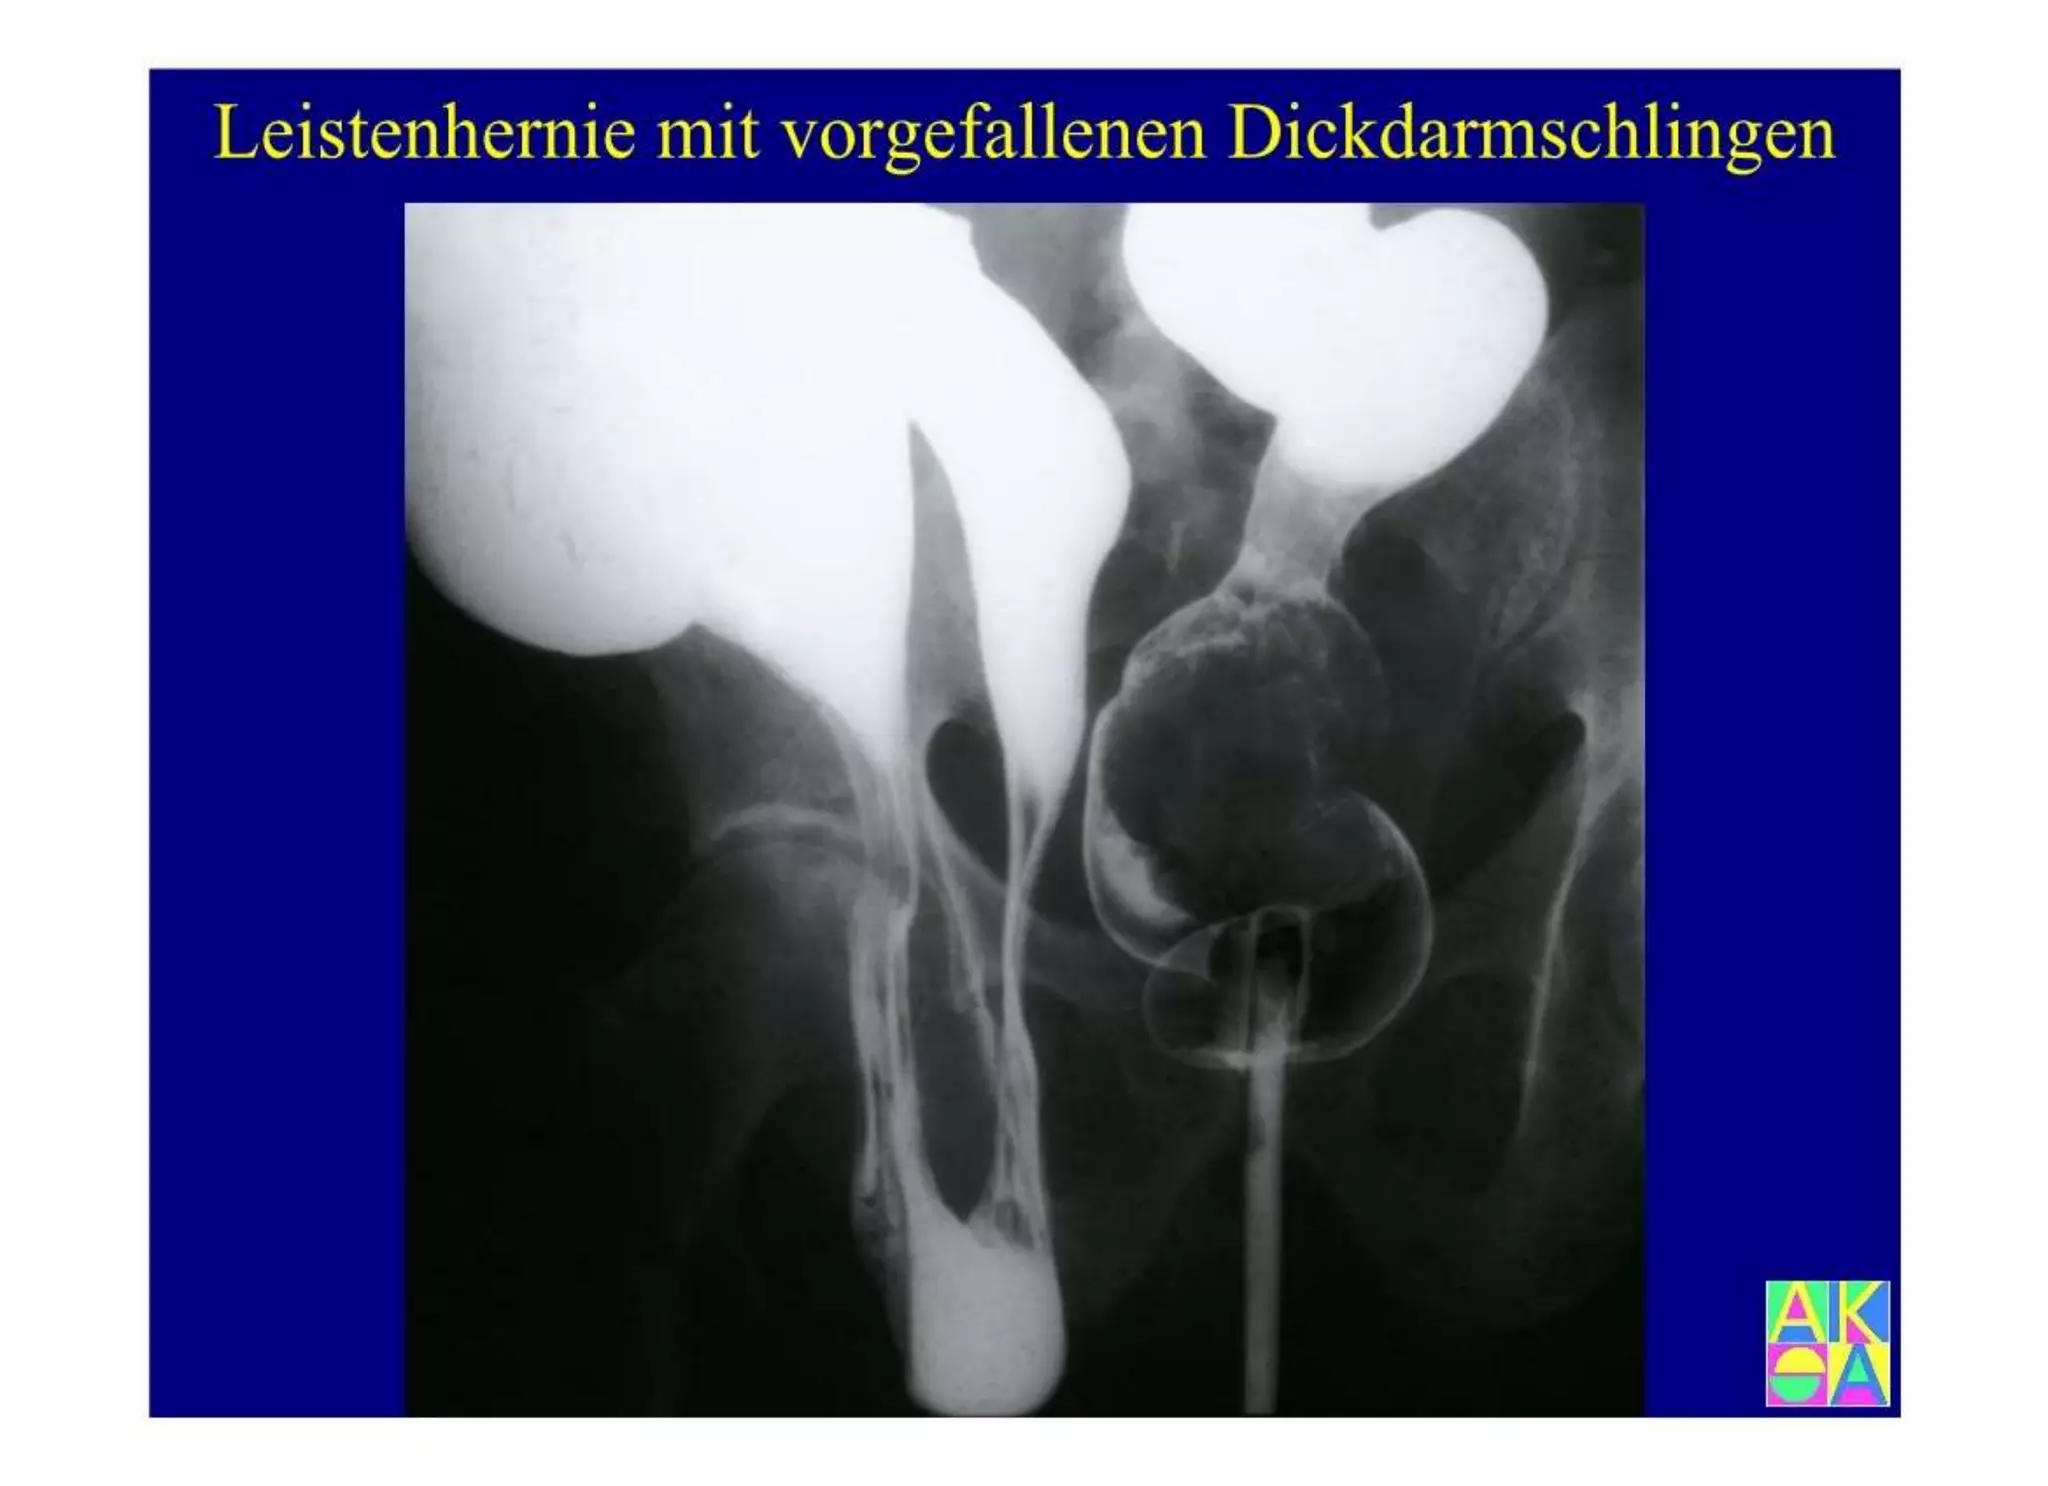

Chronische Enteropathie und Ileus, Dünndarm und Dickdarmdiagnostik, Mechanischer und paralytischer Ileus, Eingeklemmte Darmabschnitte, aufgereihter Bridenileus, und dazu Dickdarmileus, eingeklemmte Hernien, Weitergabeskript